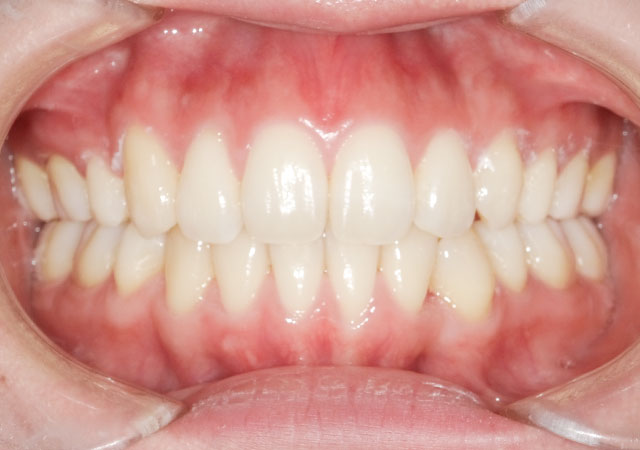

【治療内容】八重歯(叢生)の患者さんです。ホワイトワイヤー矯正で歯並びを治しました。

【費用】この方は、部分矯正でも治ったのですが、奥歯も含めて全部綺麗にしたいというご希望と、白いワイヤーで目立たない治療をご希望されたので、白いワイヤーの全体矯正を行いました。

ホワイトワイヤー矯正 795,000円(税抜)

【リスク】矯正装置が口の中にあたって口内炎が出来やすくなる方もおられます。